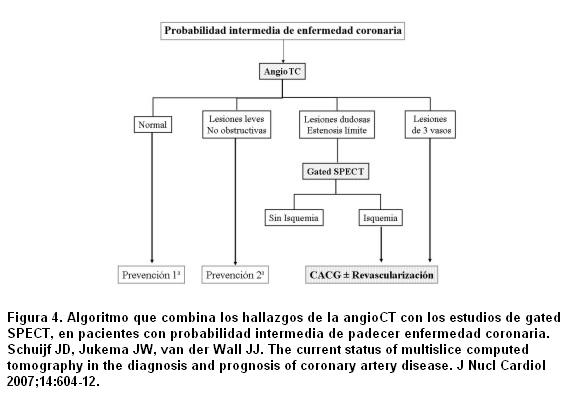

Diagnóstico de enfermedad coronaria obstructiva

Como se discutió anteriormente la angioTC tiene una excelente sensibilidad diagnóstica en los territorios proximales de las arterias coronarias >1,5 mm y serias limitaciones para estudiar las ramas más pequeñas. Por lo tanto, las imágenes híbridas ofrecen una información superior sobre todo para identificar el “vaso culpable” (44-46). Por ejemplo, Rispler y colaboradores (46) reportaron una significativa mejoría en la especificidad (63% a 95%) y del VPP (31% a 77%) para detectar EC angiográficamente cuantificada en un grupo de 56 pacientes estudiados con SPECT/angioTC. Hallazgos similares fueron mostrados por Sato y colaboradores (47), quienes reportaron la precisión diagnóstica para detectar estenosis coronaria significativa combinando la angioTC de 64 cortes con la SPECT con 201Talio. En 130 pacientes compararon la angioTC sola versus la angioTC/SPECT, el análisis mostró un incremento significativo de la especificidad (de 80% a 92%) y del VPP (de 69% a 85%) sin cambios en la sensibilidad ni en el VPN. Estos resultados indican que la angioTC puede sobreestimar la estenosis coronaria y la combinación con la SPECT permite identificar los falsos positivos de la TC (48). La especificidad y el VPP son particularmente subóptimos en presencia de artefactos de movimiento o severas calcificaciones.

Por otro lado, la angioTC mejora la detección de la EC de múltiples vasos, la cual puede ser una debilidad de los EPM, ya que ayuda a categorizar las lesiones intermedias y los defectos dudosos en la perfusión, y en una tercera parte de los pacientes el análisis de las imágenes de fusión proporciona información adicional que no es obtenida individualmente usando ambos estudios por separado. Es interesante ver que los defectos de perfusión fueron raramente observados en vasos con artefactos de movimiento, pero fueron más frecuentes en vasos severamente calcificados (59%). Por lo tanto, un segmento no evaluable por calcificaciones debería ser sometido a más estudios por su alta probabilidad de obstrucción, mientras los segmentos con artefactos de movimiento (por ejemplo, la arteria coronaria derecha) son usualmente más “benignos” (47). Sato y colaboradores (47) también proponen una guía para la elección de las pruebas diagnósticas. En pacientes con sospecha de EC, pero con una probabilidad baja o intermedia pretest, con baja prevalencia de EC según sexo y edad, la angioTC puede ser de elección debido a su alto poder predictivo negativo (97% para su serie). En presencia de un resultado dudoso o estudio no valorable (artefactos o calcificaciones) los EPM pueden detectar el significado hemodinámico de las lesiones tomográficamente relevantes o identificar las lesiones que necesiten revascularización. En pacientes con probabilidad intermedia o alta pretest, con alta probabilidad de calcificaciones coronarias, puede anticiparse un VPP bajo de la angioTC. Por lo tanto, los EPM deben ser considerados de primera línea. La angioTC puede agregar información en presencia de EPM dudosos sugestivos de artefactos de atenuación o de enfermedad microvascular (49). Nótese que la combinación de angioTC/SPECT es un procedimiento muy útil para el diagnóstico inicial de EC, pero no debe usarse en forma rutinaria en todos los pacientes. Desde un punto de vista práctico es preferible usar una sola modalidad y solo si es necesario complementar con otras pruebas a fin de mejorar la efectividad, minimizar los costos y limitar la exposición a las radiaciones (48).